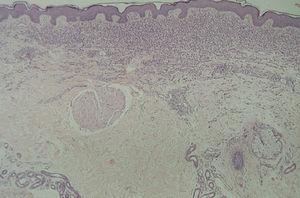

En la HCL el infiltrado se localiza normalmente en la dermis adventicial, y puede invadir la epidermis, produciendo clínicamente lesiones erosivas (figs. 13 y 14). En las formas nodulares puede invadir la hipodermis. En pacientes adultos se ha descrito la distribución del infiltrado alrededor de los anejos (figs. 15 y 16) 13. Aparecen otras células inflamatorias en número variable, sobre todo neutrófilos, eosinófilos, linfocitos y mastocitos y, en menor medida, células gigantes multinucleadas. De forma clásica se han descrito tres subtipos principales: proliferativo, granulomatoso y xantomatoso, que se intentan correlacionar con las diferentes formas clínicas. Histológicamente no existen diferencias entre la HCL y la reticulohistiocitosis congénita autoinvolutiva 7.

Fig. 15.--Infiltrado de células de Langerhans rodeando los folículos pilosos. (Hematoxilina-eosina, x10.)

Fig. 16.--Detalle del infiltrado rodeando los anejos. (Hematoxilina-eosina, x20.)